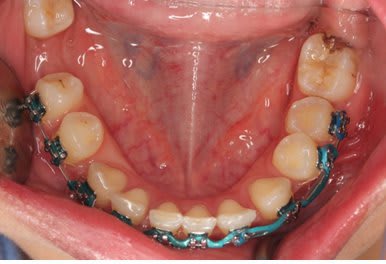

Et après environs un ans de traitement

Bingo

Il y avait ankylose de la 22 mais pas des molaires.

Sa se devine ici car le fil est quasiment droit ce qui signifie que sa forme c'est exprimé presque complètement.

Le problème étant que si la forme du fil est correct sa position ne l'est pas.

La 22 étant ankylosé elle a fonctionné comme un point d’appui et a fait bouger tout le reste.

Dans ce cas c'est impressionnant car la dent ankylosé

- était mal positionné en début de traitement

- Qu'il n'y avait aucun dent dans le secteur postérieur pour limiter les effet.

Le fil rond pouvait tourner dans le slot de 22, vue qu'il n'y avait pas de dent en postérieure rien n’empêchait la rotation du fil et donc l’aggravation de la malocclusion.

La 21 qui était proche a était la plus affecté sa se voit bien sur les photo avec bracket, elle a subit une importante rotation dans le sens mesio distal et a était procliner. Son changement de position a eu un impacte sur 21 puis sur 11 ect ect , les effets devenant de plus en plus faible a mesure que l'on s'éloigne.

On a eu une important proclination de l'ensemble des incisive.

Mais encore une fois ce qu'il faut noter c'est le changement important au niveau de 21 avec un FIL PARFAITEMENT DROIT au niveau des incisives